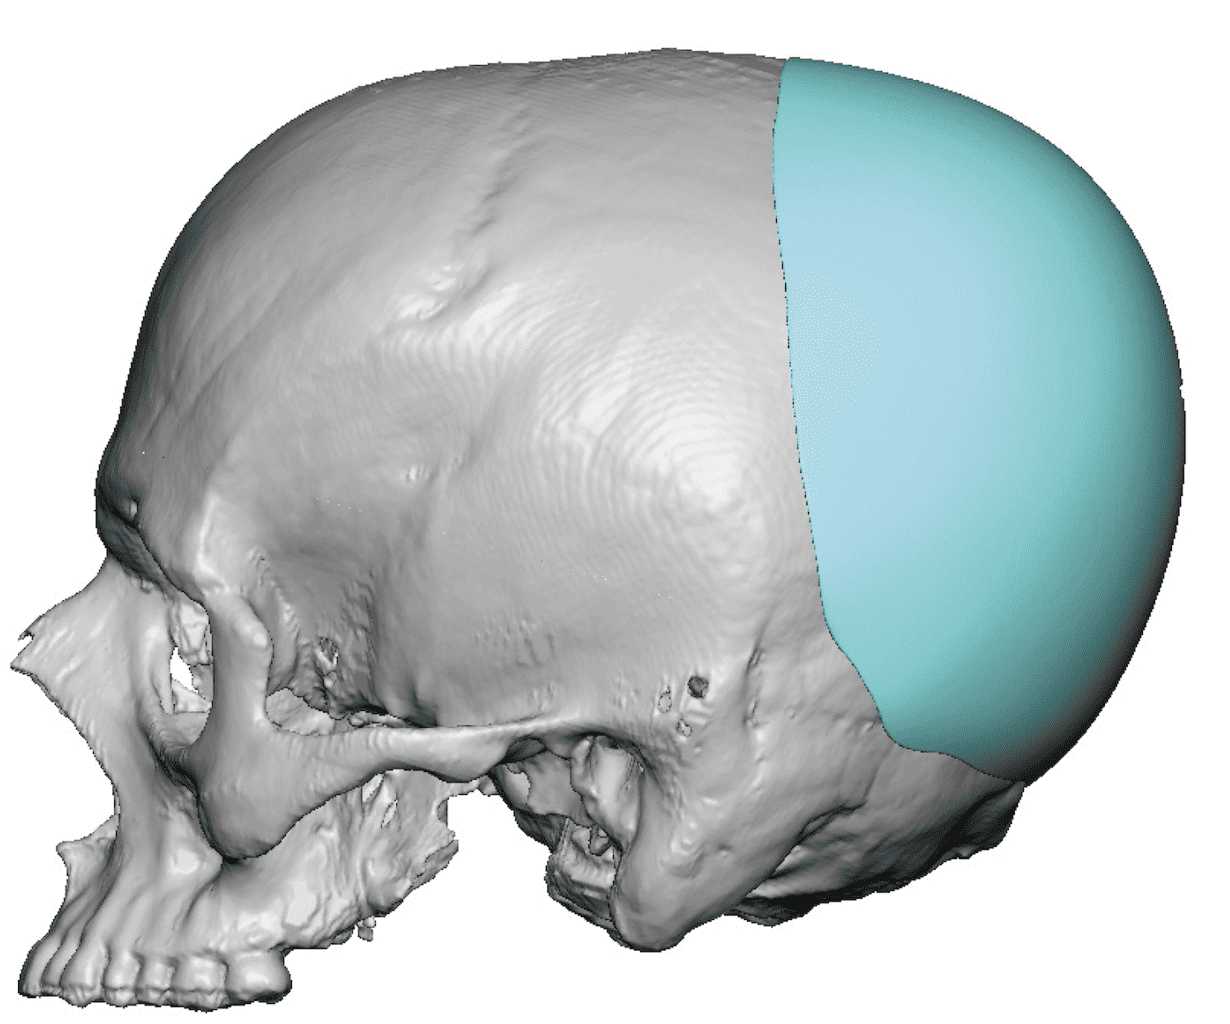

Patient 49

Desire for further skull augmentation after a primary skull implant.

Five years after an initial custom skull implant placement a new custom skull implant that increased the volume by 35% was placed.

Desire for further skull augmentation after a primary skull implant.

Five years after an initial custom skull implant placement a new custom skull implant that increased the volume by 35% was placed.